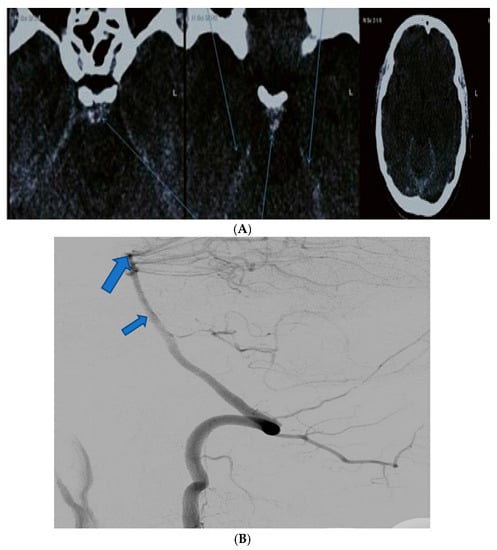

| Patient Age | Patient Sex | Presenting Symptoms | Diagnosis Method | Hunt Hess Scale at Diagnosis | Modified Fischer Scale at Diagnosis | Complications | Rankin Scale at Discharge | Given Treatment |

|---|---|---|---|---|---|---|---|---|

| 54 | F | Diplopia, headache | Native CT scan, CTA | I | I | Mild vasospasm, mild hydrocephaly | 2 | Nimodipine |

| 61 1 | M | Flaccid tetraplegia, altered Mental status | Native CT scan, DSA | IV | IV | Severe vasospasm, hydrocephalus | 6 (deceased) | Nimodipine, mannitol |

| 37 | M | Headache, diplopia | Native CT scan, DSA angiography | II | II | None | 3 | Nimodipine |

| 48 | F | 3rd nerve palsy, pupillary anomalies | Native CT scan, CTA | II | II | Mild vasospasm | 2 | Nimodipine |

| 41 2 | M | Headache, diplopia | Native CT scan, DSA | III | III | Mild vasospasm | 3 | Nimodipine, mannitol |

| 59 | M | 3rd nerve paresis, pupillary anomalies, hemiplegia | Native CT scan, DSA angiography | V | IV | Hydrocephalus, moderate vasospasm | 4 | Nimodipine, mannitol |

| 44 | F | Right internuclear ophthalmoplegia | Native CT scan, CTA | III | I | None | 1 | Nimodipine |